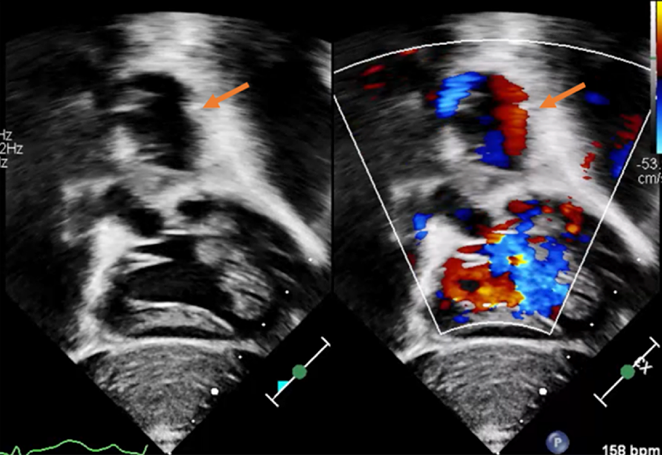

【胸部造影CT検査】mBTシャント部位に一致した動脈瘤を認めた(Fig. 2A, B).

Fig. 2 Contrast-enhanced computed tomography image of the aneurysm

A: Axial view: The aneurysm was detected just below the sternum, and the risk of rupture and bleeding was considered during the sternum incision. B: Three-dimensional reconstructed image showing an aneurysm around the modified Blalock–Taussig shunt site.